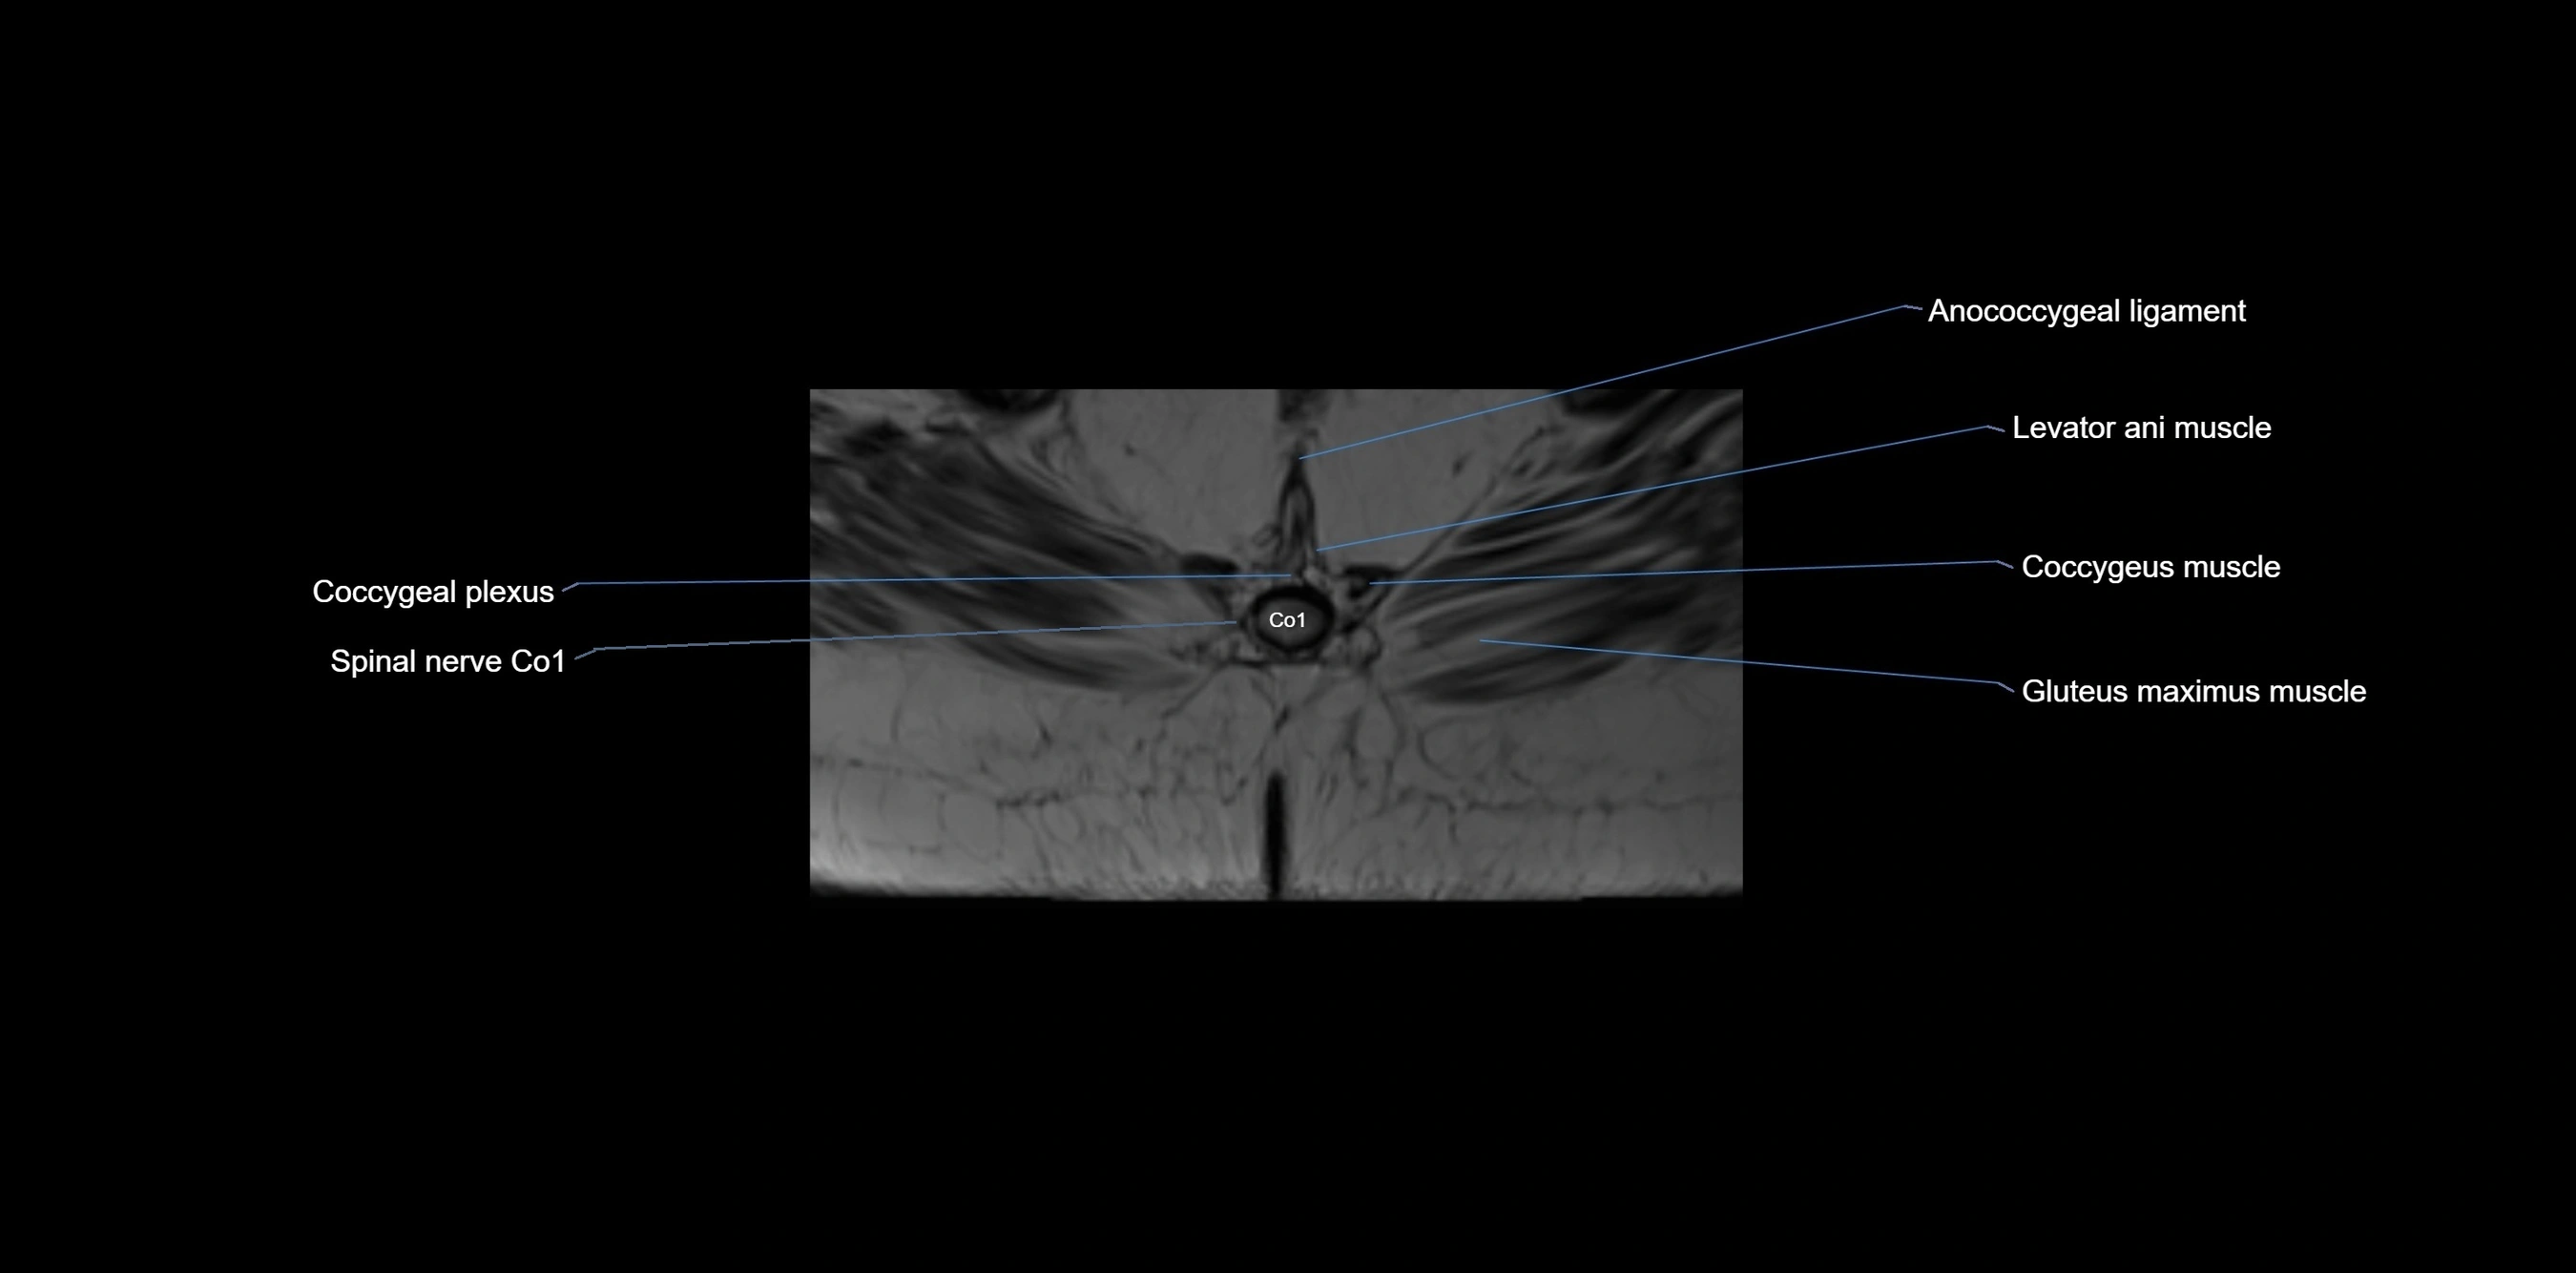

CT VRT image

image